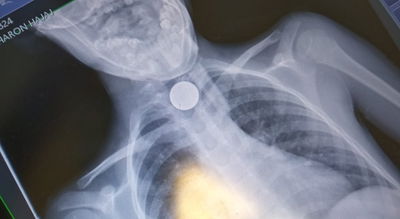

ילד חרדי, כבן 7, נחנק הערב (שלישי) בביתו שבבני ברק, לאחר שבלע מטבע של 10 אגורות; כוחות ההצלה ייצבו את מצבו ומיהרו לפנותו אל בית החולים 'מעייני הישועה' בעיר (חדשות)

אל המרכז הרפואי בצפת הגיע ילד בן 4 לאחר שבלע מטבע של 10 אגורות. הרופאים, הבהילו אותו לחדר הניתוח שם הצליחו להוציא בשלום את המטבע שנתקעה לו בוושט (בארץ)